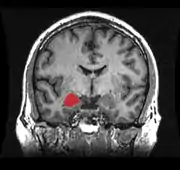

As bases neurais da agressão têm sido consistentemente estabelecidas nos últimos anos, onde regiões cerebrais e neurotransmissores, bem como as suas ligações com diversos genes, hormônios e transtornos psiquiátricos, têm sido triadas.[3][7] Dentre as estruturas corticais, o Córtex Pré-Frontal (CPF) é a região cerebral mais amplamente associada com a agressão impulsiva em humanos. O CPF desempenha um papel central no controle de comportamentos, no direcionamento a metas e na tomada de decisões. Pacientes com lesões no CPF ventromedial (CPFvm) tiveram uma maior probabilidade de mostrar confrontos verbais e agressividade, se comparados com pacientes com lesões em outras áreas cerebrais e com grupo-controle sem lesões.[19] Homens com transtorno de personalidade antissocial têm mostrado alterações no COF, no Córtex Cingulado Anterior (CCA), na Insula e na Amígdala. Similarmente, pacientes com Transtorno de Personalidade Borderline e Transtorno Explosivo Intermitente também apresentam características de funcionamento atípico nessas regiões. Estudos de neuroimagem têm confirmado uma disfunção e redução no volume do COF, CCA e CPFvm em pessoas com comportamento agressivo.[20][3]

Um número crescente de evidências tem corroborado a função da amígdala como uma das regiões cerebrais mais importantes para agressão na espécie humana. A amígdala, envolvida no processamento de estímulos biologicamente relevantes e reações emocionais, e o CPF, são reciprocamente conectados.[7][3][20] Além disso, neurotransmissores como serotonina, GABA e dopamina, e hormônios como testosterona, progesterona, cortisol e vasopressina, apresentam um relevante papel determinante para a manifestação do comportamento agressivo.[3]